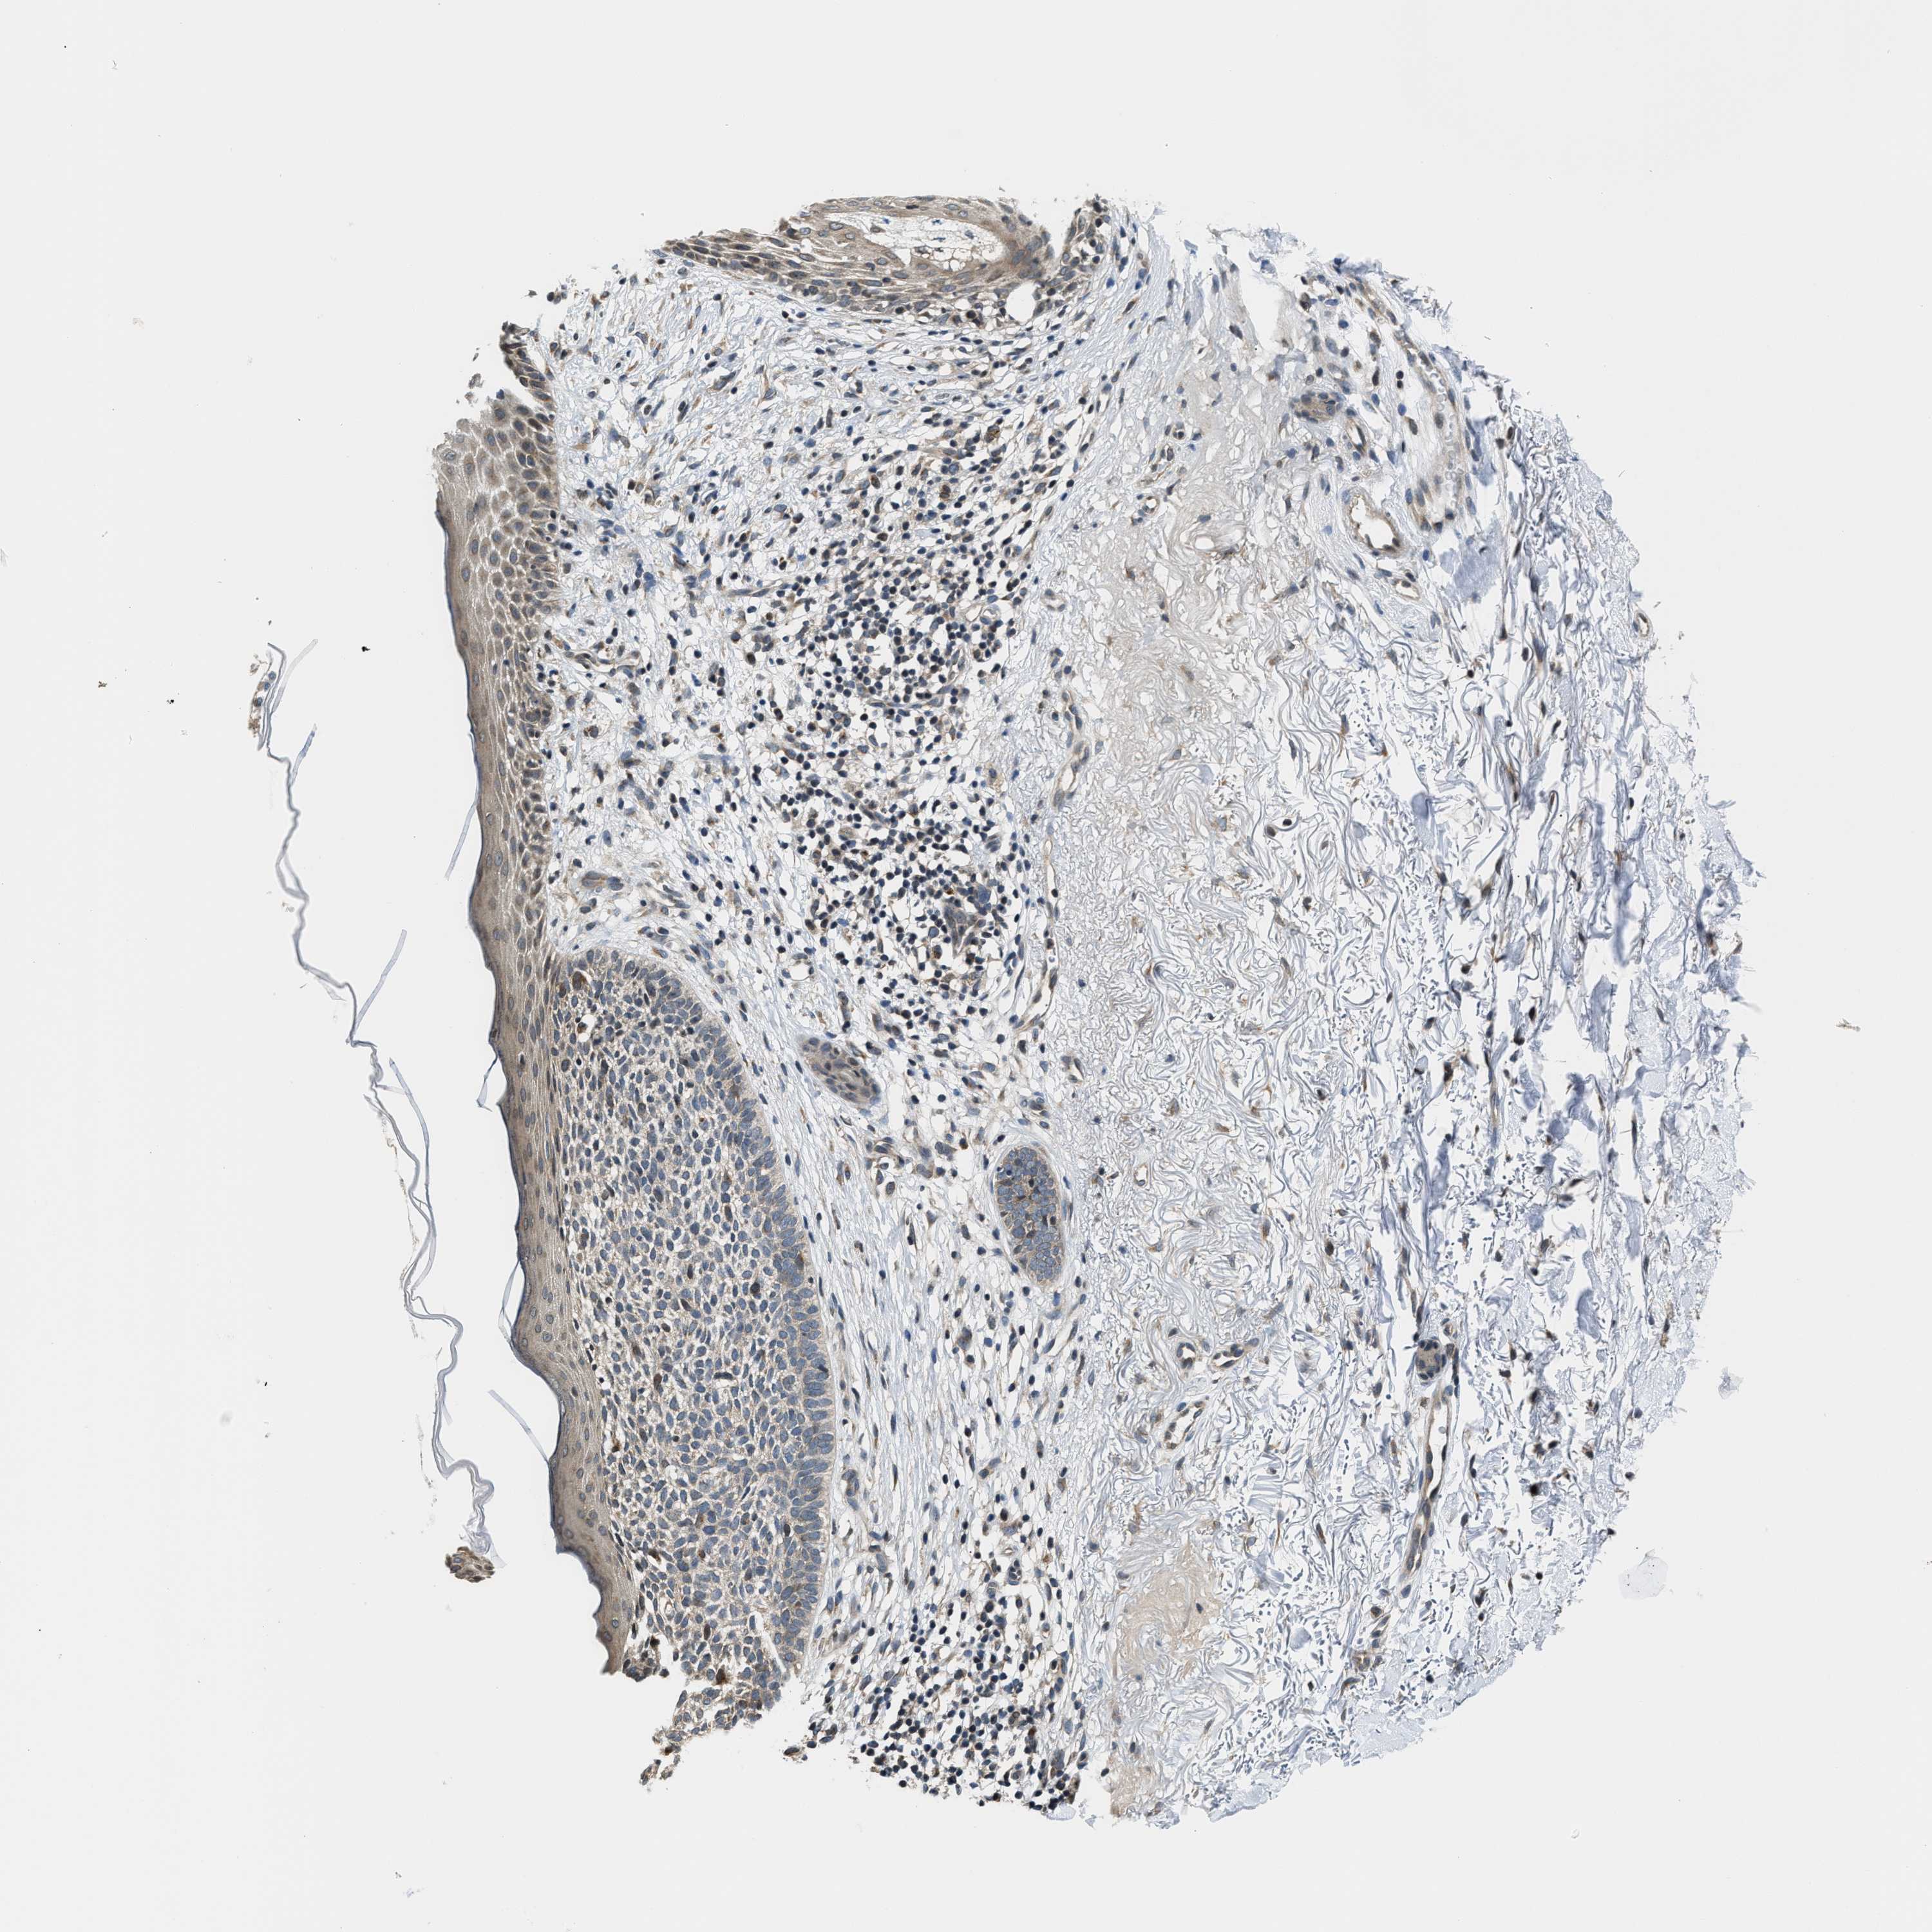

SKIN CANCER - Protein expressioni

A mouse-over function shows sample information and annotation data. Click on an image to view it in a full screen mode. Samples can be filtered based on level of antibody staining by selecting one or several of the following categories: high, medium, low and not detected. The assay and annotation is described here.

Each image is clickable and will lead to virtual microscopy that enables deeper exploration of all samples and also displays staining intensity scores, fraction scores and subcellular localization as well as patient and tissue information for each sample.

Antibody HPA026303

Not detected

Negative

None

Squamous cell carcinoma, NOS